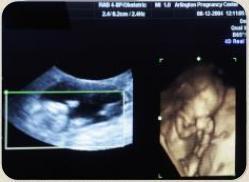

Чи допустимі шлюб і народження дітей при наявності важких генетичних захворювань?ПИТАННЯ: У мене серйозне генетичне захворювання, я постійно приймаю ліки. Незабаром збираюся виходити заміж і хочу дитину. Але лікарі відмовляють мене від цього, стверджуючи, що або дитина народиться з важкими дефектами через препарати, які я приймаю, або я повинна буду припинити терапію і тоді ризикую втратити дитину, а якщо і не втрачу, то вона народиться з таким же захворюванням. Що думає Церква з цього приводу? Знаючи про ці ризики, чи можемо ми стати матір'ю і батьком? І якщо ні, чи можемо ми взагалі укласти дійсний шлюб, знаючи, що в нас не буде дітей? І як нам оберігатися?